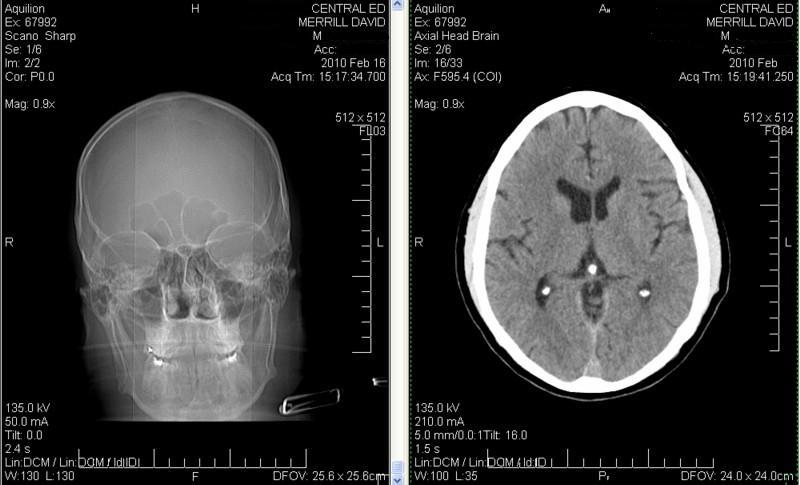

Attached Files